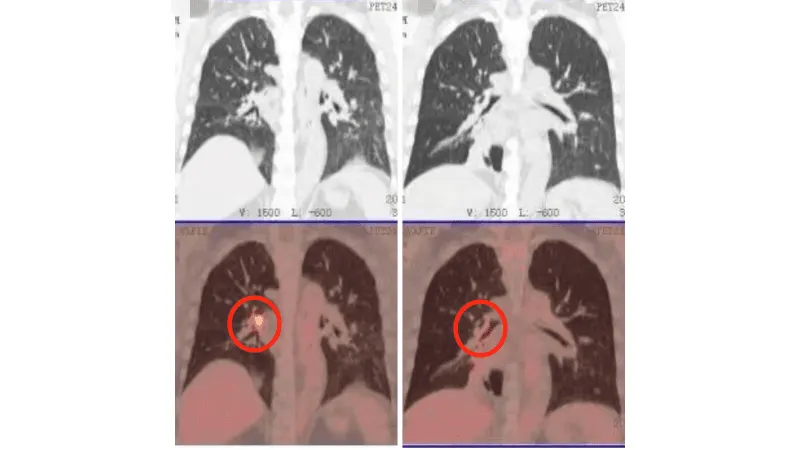

Сравнение КТ лёгких до и после лечения. Опухоль лёгких практически инактивирована

(Слева: до лечения, справа: после лечения)

Лечение дало ошеломляющие результаты: • После двух процедур КТ показало уменьшение очага в легком, а колоноскопия - значительное сокращение опухоли в кишечнике. • Исчезли мучительные симптомы: кашель и кровавый стул. • После семи сеансов опухоль в легком была практически полностью инактивирована, а в кишечнике - уменьшилась на 90%. Путь не был усыпан розами. Однажды у Радика резко упал уровень тромбоцитов, что грозило опасным кровотечением. В момент отчаяния именно настойчивость и профессионализм его лечащего врача, доктора Аденана, и всей команды спасли ситуацию. Быстро проведенная симптоматическая терапия стабилизировала состояние, и лечение было продолжено.